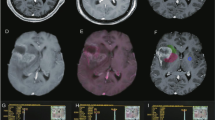

Tumours <1.5 ml generally appeared homogeneous but occasionally contained foci with low signal intensity on T2 images. Such low signal areas were seen more often in larger tumours. All tumours >2 ml had a heterogeneous appearance, containing both hyperintense and hypointense areas (Figure 1).

(A,C) Proton density-weighted MR images of two representative xenografts two (A) and three (C) weeks after cell inoculation, respectively. Scale bars=10 mm. (B) 1H MRS spectrum from tumour in A. The selected VOI is indicated by a rectangle. Cho-containing compounds dominate the spectrum. ML signals are also seen. TE=20 ms, 128 averages. (D) 1H MRS spectrum from large tumour seen in C. The VOI (rectangle in C) includes tumour tissue with variable signal intensity. There is a weak Cho signal while MLs dominate. TE=20 ms, 128 averages. B and D are not shown to scale.

In MR spectroscopy, short TE spectra (TE=20 ms) were dominated by signals from Cho at 3.2 ppm and ML signals, the latter contributing to resonances at 0.7–0.9 ppm and 1.2–1.5 ppm, respectively (Figure 1 and Figure 2).

Spectra from small xenografts (V<1.5 ml) typically had intense Cho signals together with moderate ML levels (Figure 1b). A small peak at 3.0 ppm, compatible with creatine/phosphocreatine, seemed to be present in most tumours but could not be unequivocally separated from Cho and was therefore not analysed further. The putative neuronal marker NAA (N-acetyl-aspartate) (Urenjak et al, 1992) with a chemical shift of 2.0 ppm was not distinguishable at short TEs where lipid signals overlapped with this spectral region. Neither intermediate (TE=135 ms) nor long (TE=172 ms) TEs (where lipid signals are fully relaxed) could support any presence of NAA in the xenografts (Figure 2). Spectra obtained from large tumours (V>2 ml) generally displayed a ML peak of high intensity at 1.2–1.4 ppm, a variable lipid peak at 0.9 ppm and a less prominent Cho signal (Figure 1 and Figure 2). Control spectra obtained from skeletal muscle showed a prominent creatine peak (only weakly present in tumour spectra) and a modest Cho signal (Figure 3).